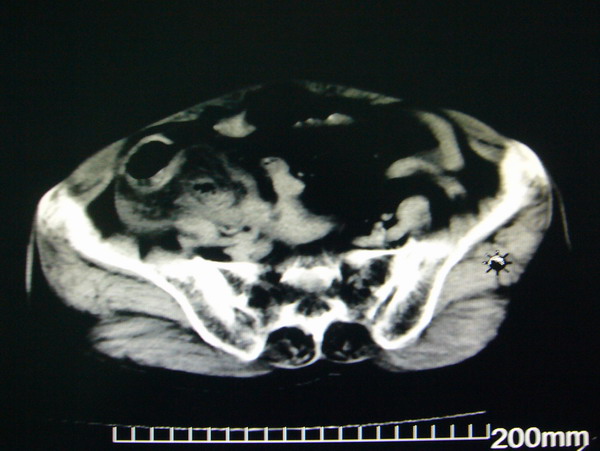

女:83y,转移性右下腹痛2小时,白细胞计数增高。

1.右侧肾盂扩大,肾盏无扩张,考虑:先天性肾盂变异可能性大。

2.胆囊扩张,考虑:胆囊炎。

3.阑尾区域可见以结节样高密度影,结合病史,考虑:阑尾结石,阑尾炎。

右下腹肠系膜增厚,结合病史支持阑尾炎.

右侧壶腹型肾盂可能,建议输路造影或增强

1.右侧肾盂扩大,考虑先天性肾盂变异或肾盂旁囊肿。

2.胆囊扩张,考虑胆囊炎。

3.阑尾区域可见结节样高密度影,结合病史考虑:阑尾结石、阑尾炎。